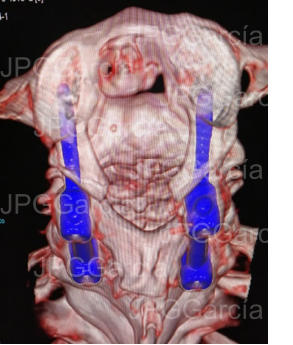

ESTUDIO DE CONTROL TOMOGRÁFICO CON COLOCACIÓN DE TORNILLOS Y BARRAS AL ATLAS Y AXIS